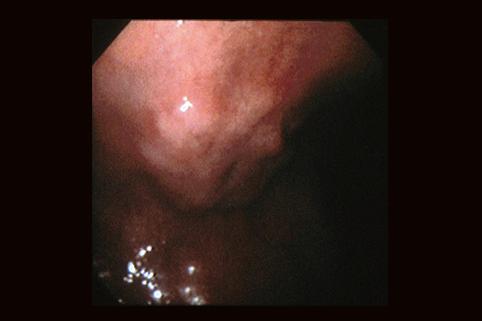

clasificación del pacienteTumor Epitelial Maligno/Adenocarcinoma

parte(separada por órganos)estómago(región)/ángulo

método de exámenEndoscopia

clasificación ectoscópica de tumoresTipo 0(tipo superficial)/Tipo IIa(IIa+IIc)

diámetro mayor del tumor30 - 34

grado de penetraciónm